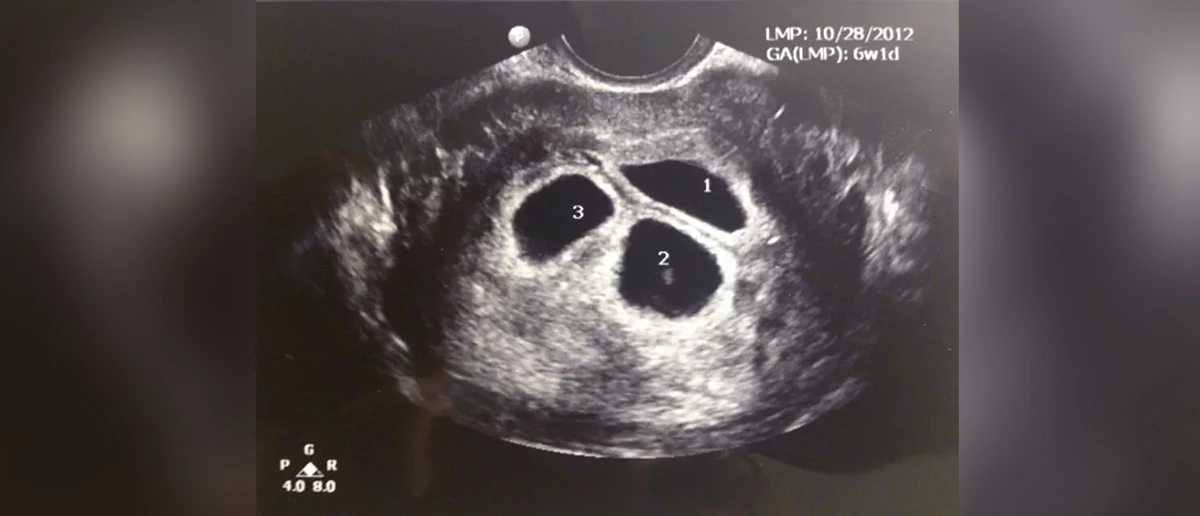

În tratamentele FIV, în sarcinile triplete sau cvadruplete rezultate din transferul multiplu de embrioni, numărul sarcinilor poate fi redus prin aplicarea tehnicii de reducere fetală pentru viitorul sănătos al mamei și al bebelușilor. Multe paciente care sunt insarcinate cu mai mult de o sarcina gemelara recurg la aceasta metoda pentru a avea o sarcina usoara si sanatoasa si in acelasi timp pentru a reduce riscul nasterii premature.

Reducerea fetala se realizeaza intre saptamana a 11-a si a 12-a de sarcina. Procedura se efectuează sub anestezie cu ajutorul ultrasunetelor din abdomen sau vagin. Sacul gestational se examineaza si se termina prin aspirarea sacului, care se decide a fi terminat, cu ajutorul unui ac subtire sau prin injectarea unui medicament care contine potasiu in cavitatea inimii bebelusului cu ajutorul unui ac. Nu este necesar să avortați copilul după procedură. Copilul se micșorează în interiorul corpului în timp și de obicei dispare. Riscul de a pierde alți bebeluși după reducerea fetală este de 1-5%.